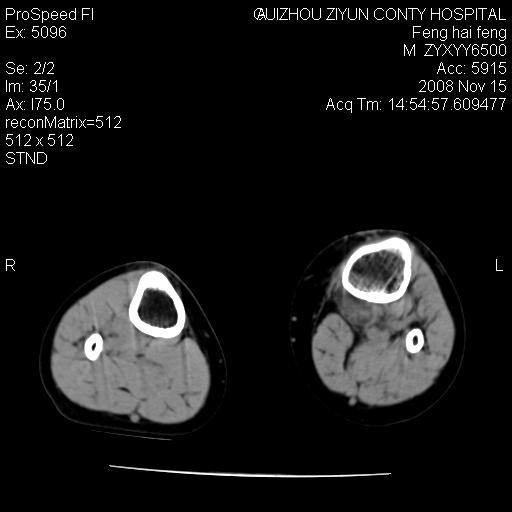

标题: CT16656:M 14Y 左膝关节肿胀一年余。其余病史不详。 [打印本页]

标题: CT16656:M 14Y 左膝关节肿胀一年余。其余病史不详。

考虑左侧髌骨结核;左膝关节滑膜肿胀、增厚,关节囊积液。

左膝滑膜型关节结核可能性大!支持!滑膜型关节结核主要ct表现:关节囊肿胀,积液,关节面见小破坏灶,并见点状死骨!

好大的左腿!考虑左侧髌骨结核,左膝关节滑膜肿胀、增厚,关节囊积液。

左侧髌骨结核;左膝关节滑膜肿胀、增厚,关节囊积液